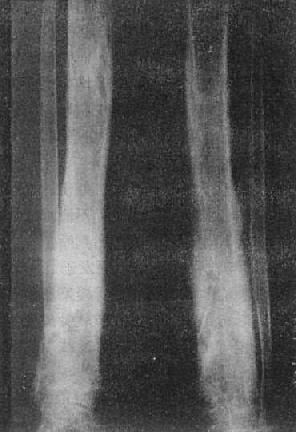

图2-1-8 前臂小腿骨骨质软化—佝偻病骨质普遍密度减低,骨皮质薄,边缘不清,骨小梁

模糊,骨变弯、变形。干骺端宽大呈杯口状变形,骺与干骺干骺端距离增宽。骺边缘模糊。腕骨出现少

骨质软化的X线表现主要是由于骨内钙盐减少而引起的骨密度减低,以腰椎骨盆为明显。与骨质疏松不同的是骨小梁和骨皮质边缘模糊,系因骨组织内含有大量未经钙化的骨样组织所致(图2-1-8)。由于骨质软化,承重骨骼常发生各种变形(图2-1-9)。此外,还可见假骨折线,表现为宽约1~2mm的光滑透明线,与骨皮质垂直,边缘稍致密,好发于耻骨支肱骨股骨上段和胫骨等。

在成骨过程中,骨样组织的钙盐沉积发生障碍,即可引起骨质软化。造成钙盐沉积不足的原因可以是维生素D缺乏,肠道吸收功能减退,肾排泄钙磷过多和碱性磷酸酶活动减低。骨质软化系全身性骨病,常见者发生于生长期为佝偻病,于成年为骨软化症。亦可见于其他代谢性和氟中毒骨疾患。